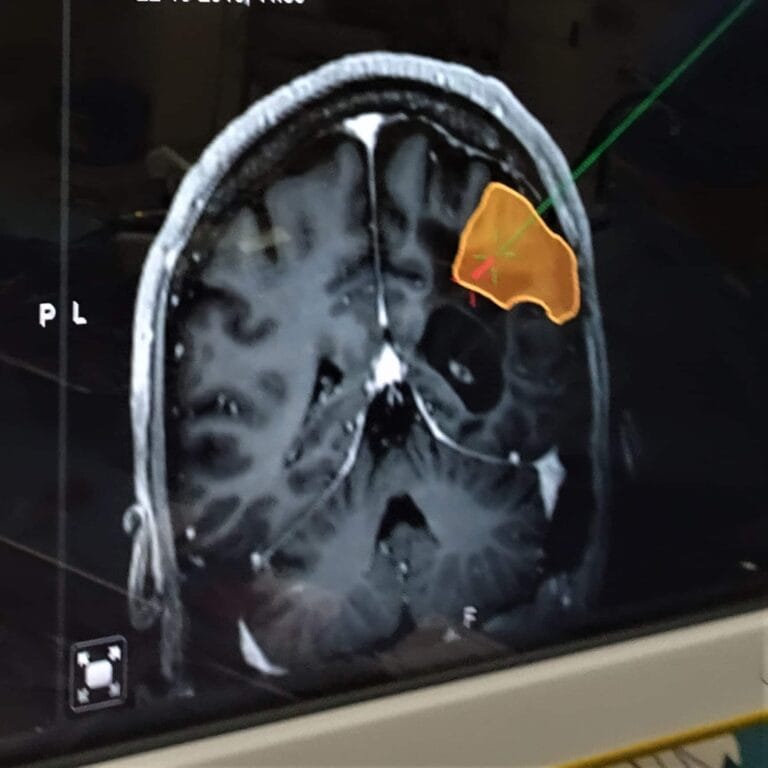

Diepteregistratie ervaring voor epilepsiechirurgie

Epilepsiechirurgie ervaring na twee operaties

Epilepsie en de risico’s bij een operatie mijn ervaring